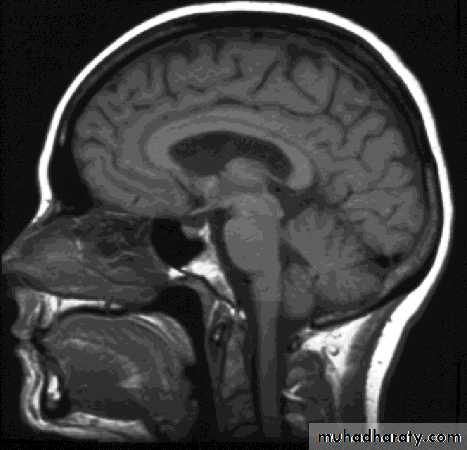

Magnetic Resonance Imaging (MRI)Magnetic Resonance Imaging (MRI)

Uses non-ionizing radiation and has no demonstrated adverse biological effects.Magnetic resonance images can be obtained in any tissue plane

transverse

sagitttalcoronal

ComparisonsMRI image

CAT image

head

Compare bone and soft tissue density